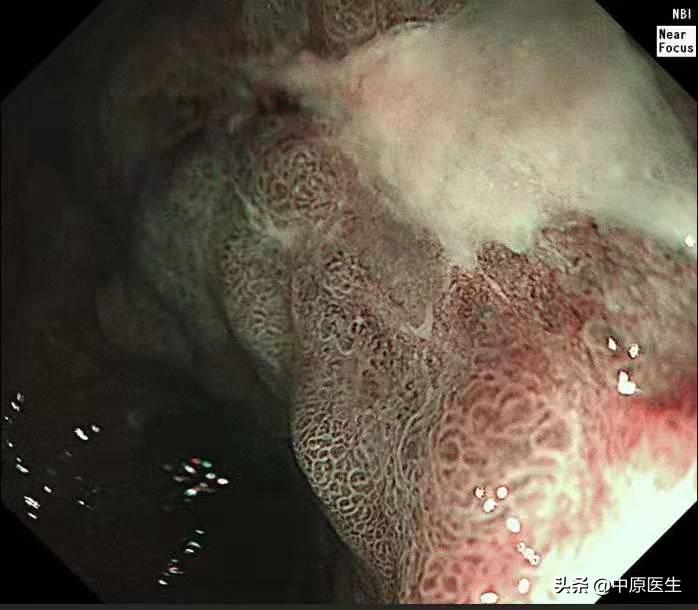

这个患者的溃疡多发,不算太大,并且表面的苔很干净,底部也算平坦,尤其是新发现的两个溃疡,从这几个条件来看,似乎良性可能性大。但是,我还是不放心。我现在只是用了白光检查,为什么不选择窄带光,放大检查?虽然麻烦一点,但是,可以看到更多细节!于是,我打开NBI模式,并且使用变焦(俗称放大,可以达到和显微镜下看类似的效果),再仔细地对每一处病变进行了观察,结果竟然发现,虽然范围很小,尤其是胃窦处的溃疡,不超过2个毫米的范围内我都发现了腺管缺失和血管异常扩张的地方,这往往提示病变有可能已经癌变,在放大镜的引导下,我对病变进行了精准活检。